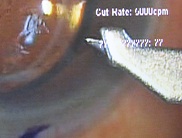

黄斑円孔の手術に関しては、?で記載しましたが、簡単におさらいすると、目の中に器械をいれて、内境界膜という網膜の表層の膜を剥離し、網膜を柔らかくします。その後、目の中に空気を入れてうつ伏せをすることで、円孔の周囲の網膜を浮力で引き寄せて、穴を閉じる。という方法です。